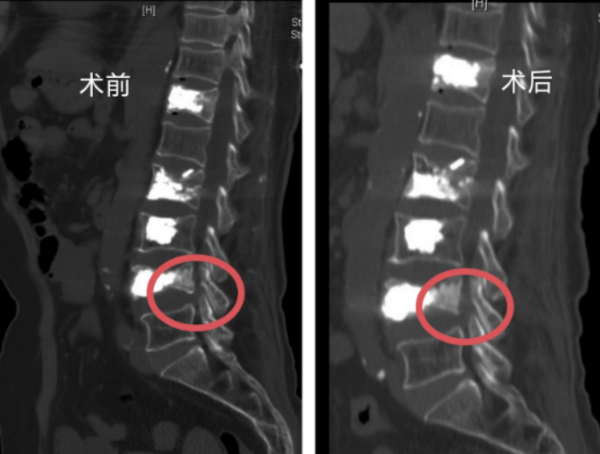

脊柱外科一区主任许宇霞接诊后,综合分析患者腰腿痛应该仍与骨折椎体有关。张纯华入院后接受CT及核磁共振检查,许宇霞发现其腰4椎体下缘近椎间孔处有一活动性骨块,当张纯华站立行走时,骨块因椎间盘形态改变移位,刺激出口神经根,导致她出现腰臀部及左下肢麻、胀、痛症状,且在活动后症状加剧。查明病因后,许宇霞主任团队很快为老人实施了椎间孔镜下腰椎减压术,取出了部分骨块,松解了受压的神经根,手术顺利完成。

核磁影像术前术后骨块对比

“脊柱骨折后一定要完善相关检查,很多患者认为做了X线检查后,再做核磁共振、CT检查是重复检查,费钱又费时间。需要明白的是,CT检查可以明确骨折的性质,是否为爆裂骨折,是否有椎体后缘骨块侵入椎管压迫神经,磁共振的优势是可以发现有无神经受压,受压是否严重,这个优势是无法替代的。”许宇霞强调,该患者就是在做了核磁共振及CT后,确诊有活动性骨块移位到椎间孔,压迫了坐骨神经。诊断明确后,即可在椎间孔镜下解决问题。